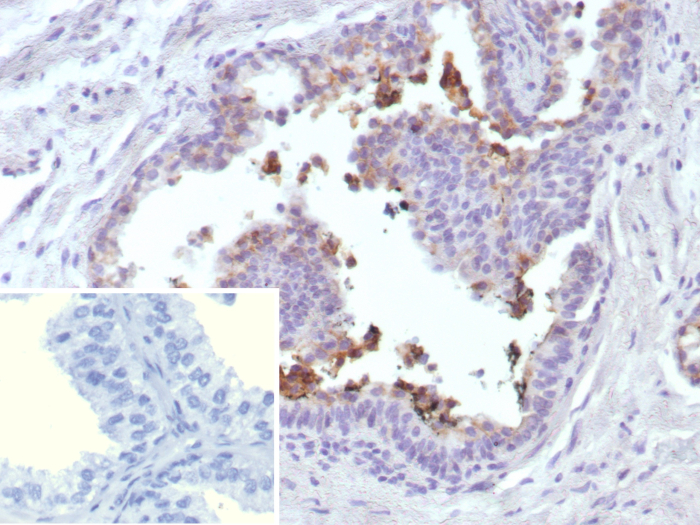

Formalin-fixed, paraffin-embedded human prostate cancer stained with ABCC4 Mouse Monoclonal Antibody (ABCC4/9018). Inset: PBS instead of primary antibody; secondary only negative control.

Positive Control

Widely expressed, with particularly high levels in prostate, but is barely detectable in liver.

IHC-P         More Details

Immunohistochemistry (Formalin-fixed) (1-2ug/ml for 30 minutes at RT)

(Staining of formalin-fixed tissues requires heating tissue sections in 10mM Tris with 1mM EDTA, pH 9.0, for 45 min at 95°C followed by cooling at RT for 20 minutes)